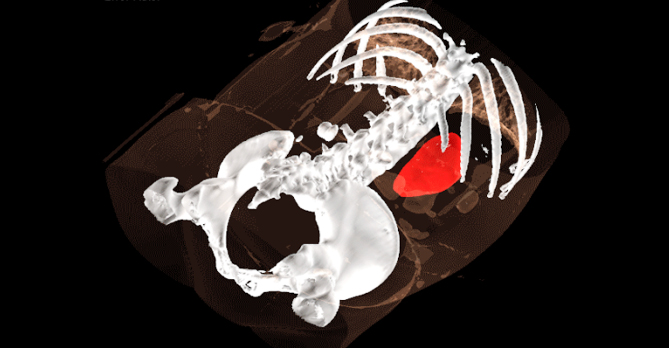

基于AI配准的多模态影像2D-3D联动

更精准的实时呈现病灶位置